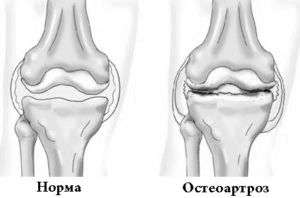

Рідше остеоартроз колінного суглоба проявляється у населення у віці тридцяти років. Суглобовий хрящ є першою ділянкою ураження. Суглоб є утворенням суглобових поверхонь кісток, які покриває хрящова тканина. У процесі життєдіяльності людини хрящова тканина руйнується під дією постійних навантажень на суглоби. Зазвичай пошкоджується колінний статут. Остеоартроз колінного суглоба починає розвиватися при порушенні положення рівноваги в період відновлення хряща і його руйнування. В результаті хрящ стає крихким, поступово втрачаючи еластичність і приводячи до повного руйнування суглоба.

Кісткова тканина, що знаходиться під суглобом, зазнає змін при цьому захворюванні: утворюється кістковий виріст, деформуючий суглоб.

Захворювання має стадійним характером. Для кожного ступеня характерні певні симптоми.